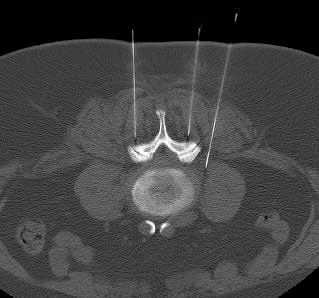

Anschließend wird die eigentliche Behandlungsnadel im genau vorgeplanten Winkel, in der richtigen Höhe der Wirbelsäule millimetergenau bis an Nervenwurzel und das Wirbelgelenk vorgeschoben. Dies ist nahezu schmerzfrei – man spürt „einen Druck“ im Rücken. Das anschließend angefertigte Kontroll-CT-Schnittbild zeigt eine korrekte Lage der Behandlungsnadel. Erst jetzt wird das Medikament exakt positioniert.